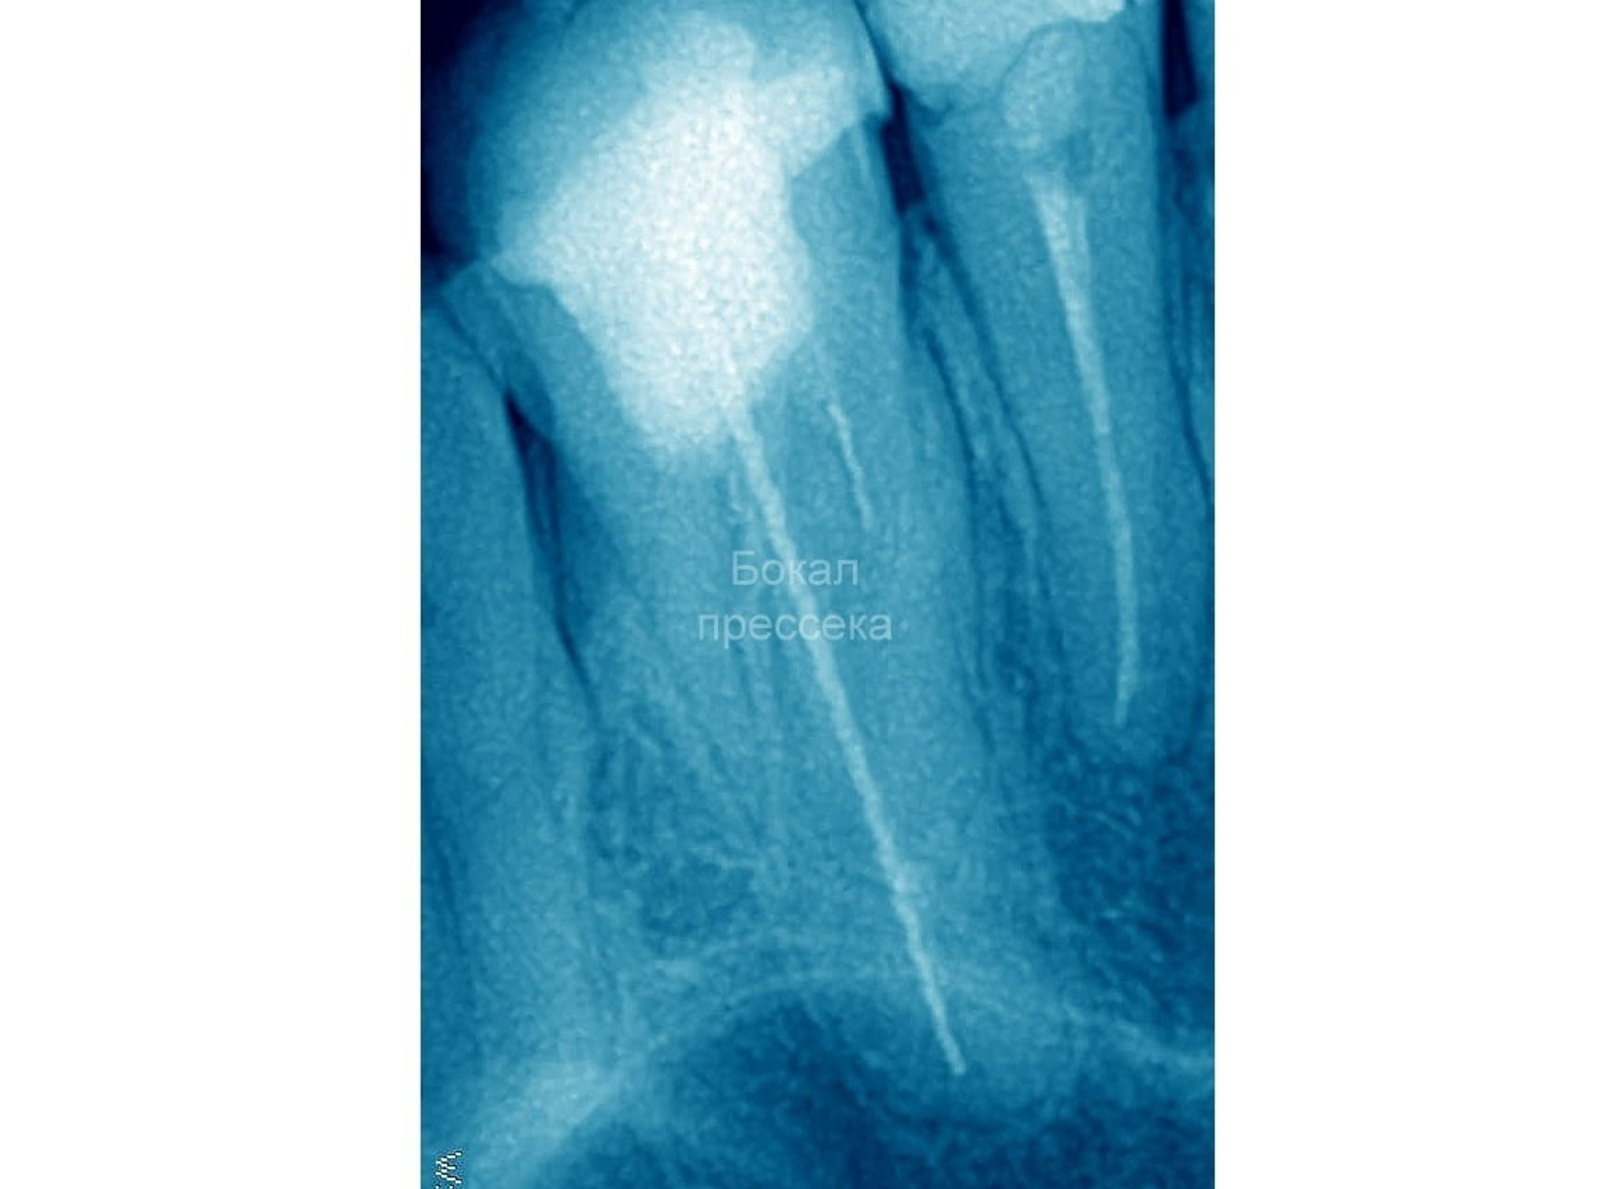

Түбәнге Новгородта стоматолог-ортопед бер ханымдың тешендә осраҡлы рәүештә ике сантиметрлыҡ энә тапҡан, тип хәбәр итә pravda-nn.ru. Билдәле булыуынса, «табышты» планлы дауаланыу ваҡытында рентген аппараты күрһәткән.

Портал хәбәр итеүенсә, энәне бер нисә йыл элек икенсе белгес «онотоп ҡалдырған». Пациент уны бөтөнләй һиҙмәй йөрөгән.